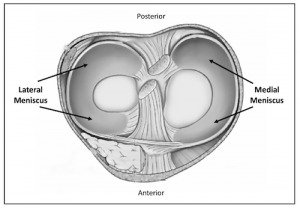

Meniscus

The meniscus is a tough, smooth, rubbery C-shaped piece of cartilage (fibrocartilage) that is wedged shaped in profile, and sits between the cartilage surfaces of the bones. It distributes your body weight more evenly across the knee joint and improves the stability of the joint. Each knee has two menisci, the medial (inside) and the lateral (outside). They are physically attached to the top of the shin bone (tibia) and make contact with the thigh bone (femur). They act as shock absorbers during weight-bearing activities.

- The front ⅓ is called the “anterior horn”.

- The middle ⅓ is called the “body”.

- The back ⅓ is called the “posterior horn”.

The wedged shaped profile helps maintain the stability of the joint by keeping the rounded femur surface from sliding off the flat tibial surface. The meniscus is nourished by small blood vessels coming in from the outer edges (vascular zone, or red zone). The meniscus also has a large area in the inner ⅓ that has no direct blood supply (avascular zone, or white zone). Between these zones is an area where the blood supply is minimal, called the red/white zone.